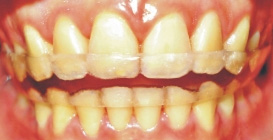

戴用維護器的措施,與「買保險」的 觀念雷同;斷然少戴用或在不該停止戴用時停止戴用維護器,實質上是個冒險行為 ( 下圖 ) ,不當戴用維護器而已導致牙齒復發時,復發之牙齒是不易簡易修復的。